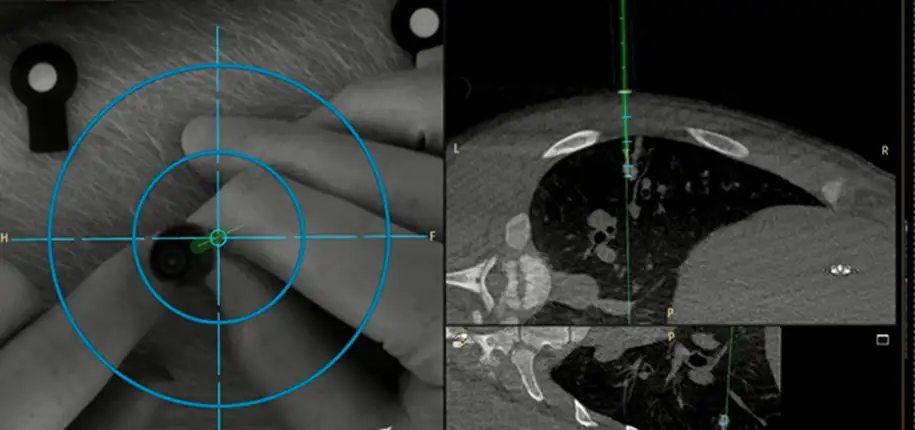

Researchers in the Interventional Radiology Research and Simulation Lab (IR-TRSL)are using AR technology developed by Philips Healthcare to display and track a digital image of their needle as it is advanced through a phantom or simulated patient. The augmented reality system also overlays images from a CT or MRI of the simulated patient onto a large monitor display so that the digital image of the needle can be advanced to its intended target while avoiding nearby vital structures. The interventional radiology researchers have teamed up with their surgery colleagues to practice using the augmented reality system for spine surgery (the placement of sacral nerve stimulators) and the localization and removal of lung tumors. There are so many more possibilities we have yet to utilize.

This augmented reality technology should be approved by the FDA for clinical use in 2020. Once approved, the technology will immediately be available for interventional radiologists and surgeons to use in our Hybrid operating room here at Cincinnati Children’s. What does all of this mean for patients? This augmented reality technology will enhance some current interventional radiology techniques and image-guided surgery procedures, making them more precise, safer, and less invasive overall.